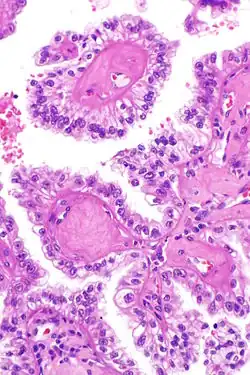

| Micrograph showing the characteristic hyalinized papillary cores found in some hereditary leiomyomatosis and renal cell carcinoma syndrome-associated renal cell carcinomas. H&E stain. | |

The renal cell carcinoma tends to be of the papillary (type 2) form and tends to occur more commonly in women than men with this syndrome. These cancers present earlier than is usual for renal cell carcinomas (typically in the twenties and thirties) and tend to be at relatively advanced stages at presentation. Tumours have rarely been reported in children. These tumours occur in ~20% of those with this mutation suggesting that other factors are involved in the pathogenesis.

The renal cell carcinomas have prominent eosinophilic nucleoli surrounded by a clear halo.